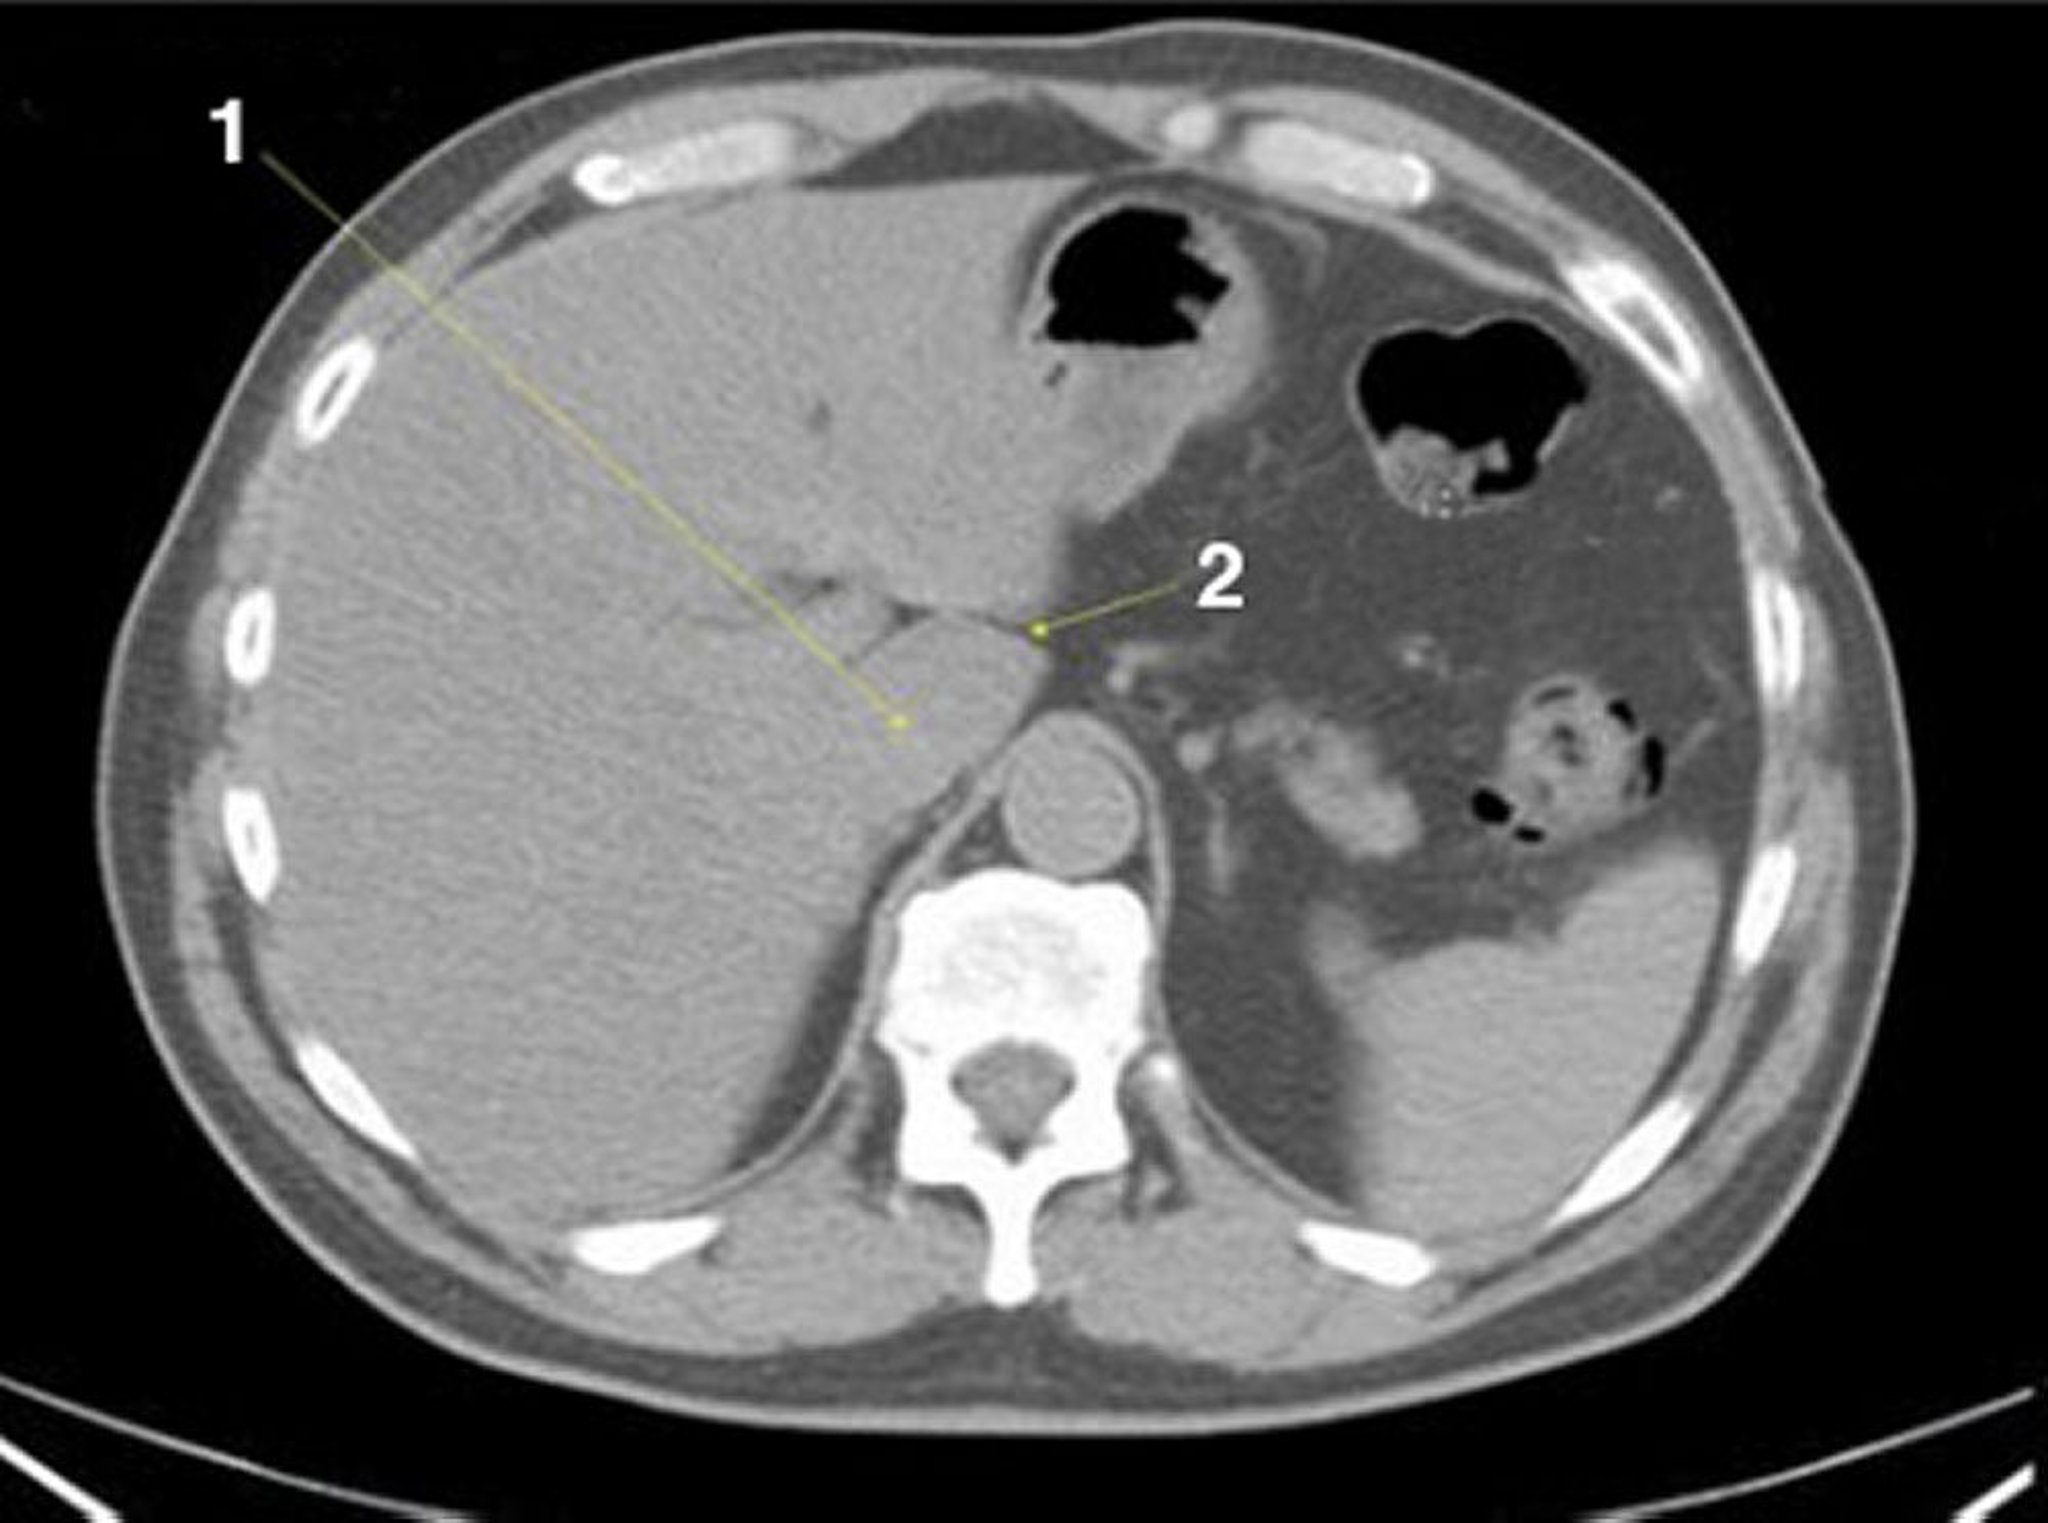

TDM sans contraste de l'abdomen et du bassin montrant une anatomie normale (diapositive 4)

1 = lobe caudé du foie; 2 = fissure du ligamentum venosum (fissure du ligament veineux).